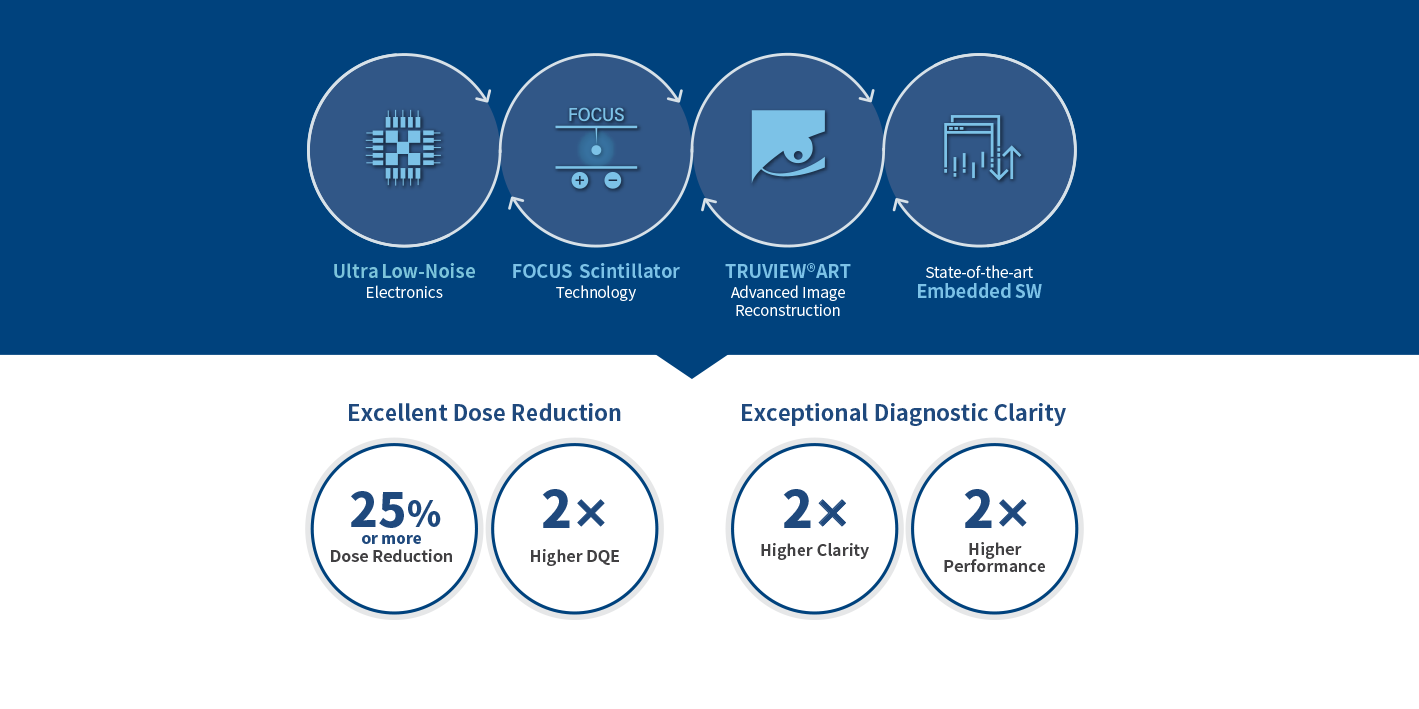

Actualizaciones tecnológicas en EVS

Advanced Series

La serie EVS Advanced proporciona una excelente experiencia de imagen en reducción de dosis y claridad diagnóstica.

Tecnología de centelleo de enfoque

FOCUS (estructura mejorada CsI óptica fluorescente) tiene una señal óptica más enfocada en comparación con CsI convencional. Como resultado, la tecnología FOCUS logra un ruido ultrabajo.

2 veces mayor DQE en dosis bajas

EXPRIMER Advanced Series proporciona una alta calidad de imagen con un 50 % menos de dosis que CR y un 25 % o más de dosis reducida en comparación con DR.

Experimente la reducción de la dosis del paciente

La dosis reducida para el paciente se logra a través del potente rendimiento de dosis baja de EXPRIMER Advanced Series.

TRUVIEW®ART

RUVIEW®ART proporciona un contraste de imagen aumentado en un 30 % o más y una mejor capacidad de detección de microanomalías en los pulmones, el tórax y el corazón.

Visibilidad 2X para una claridad de diagnóstico excepcional